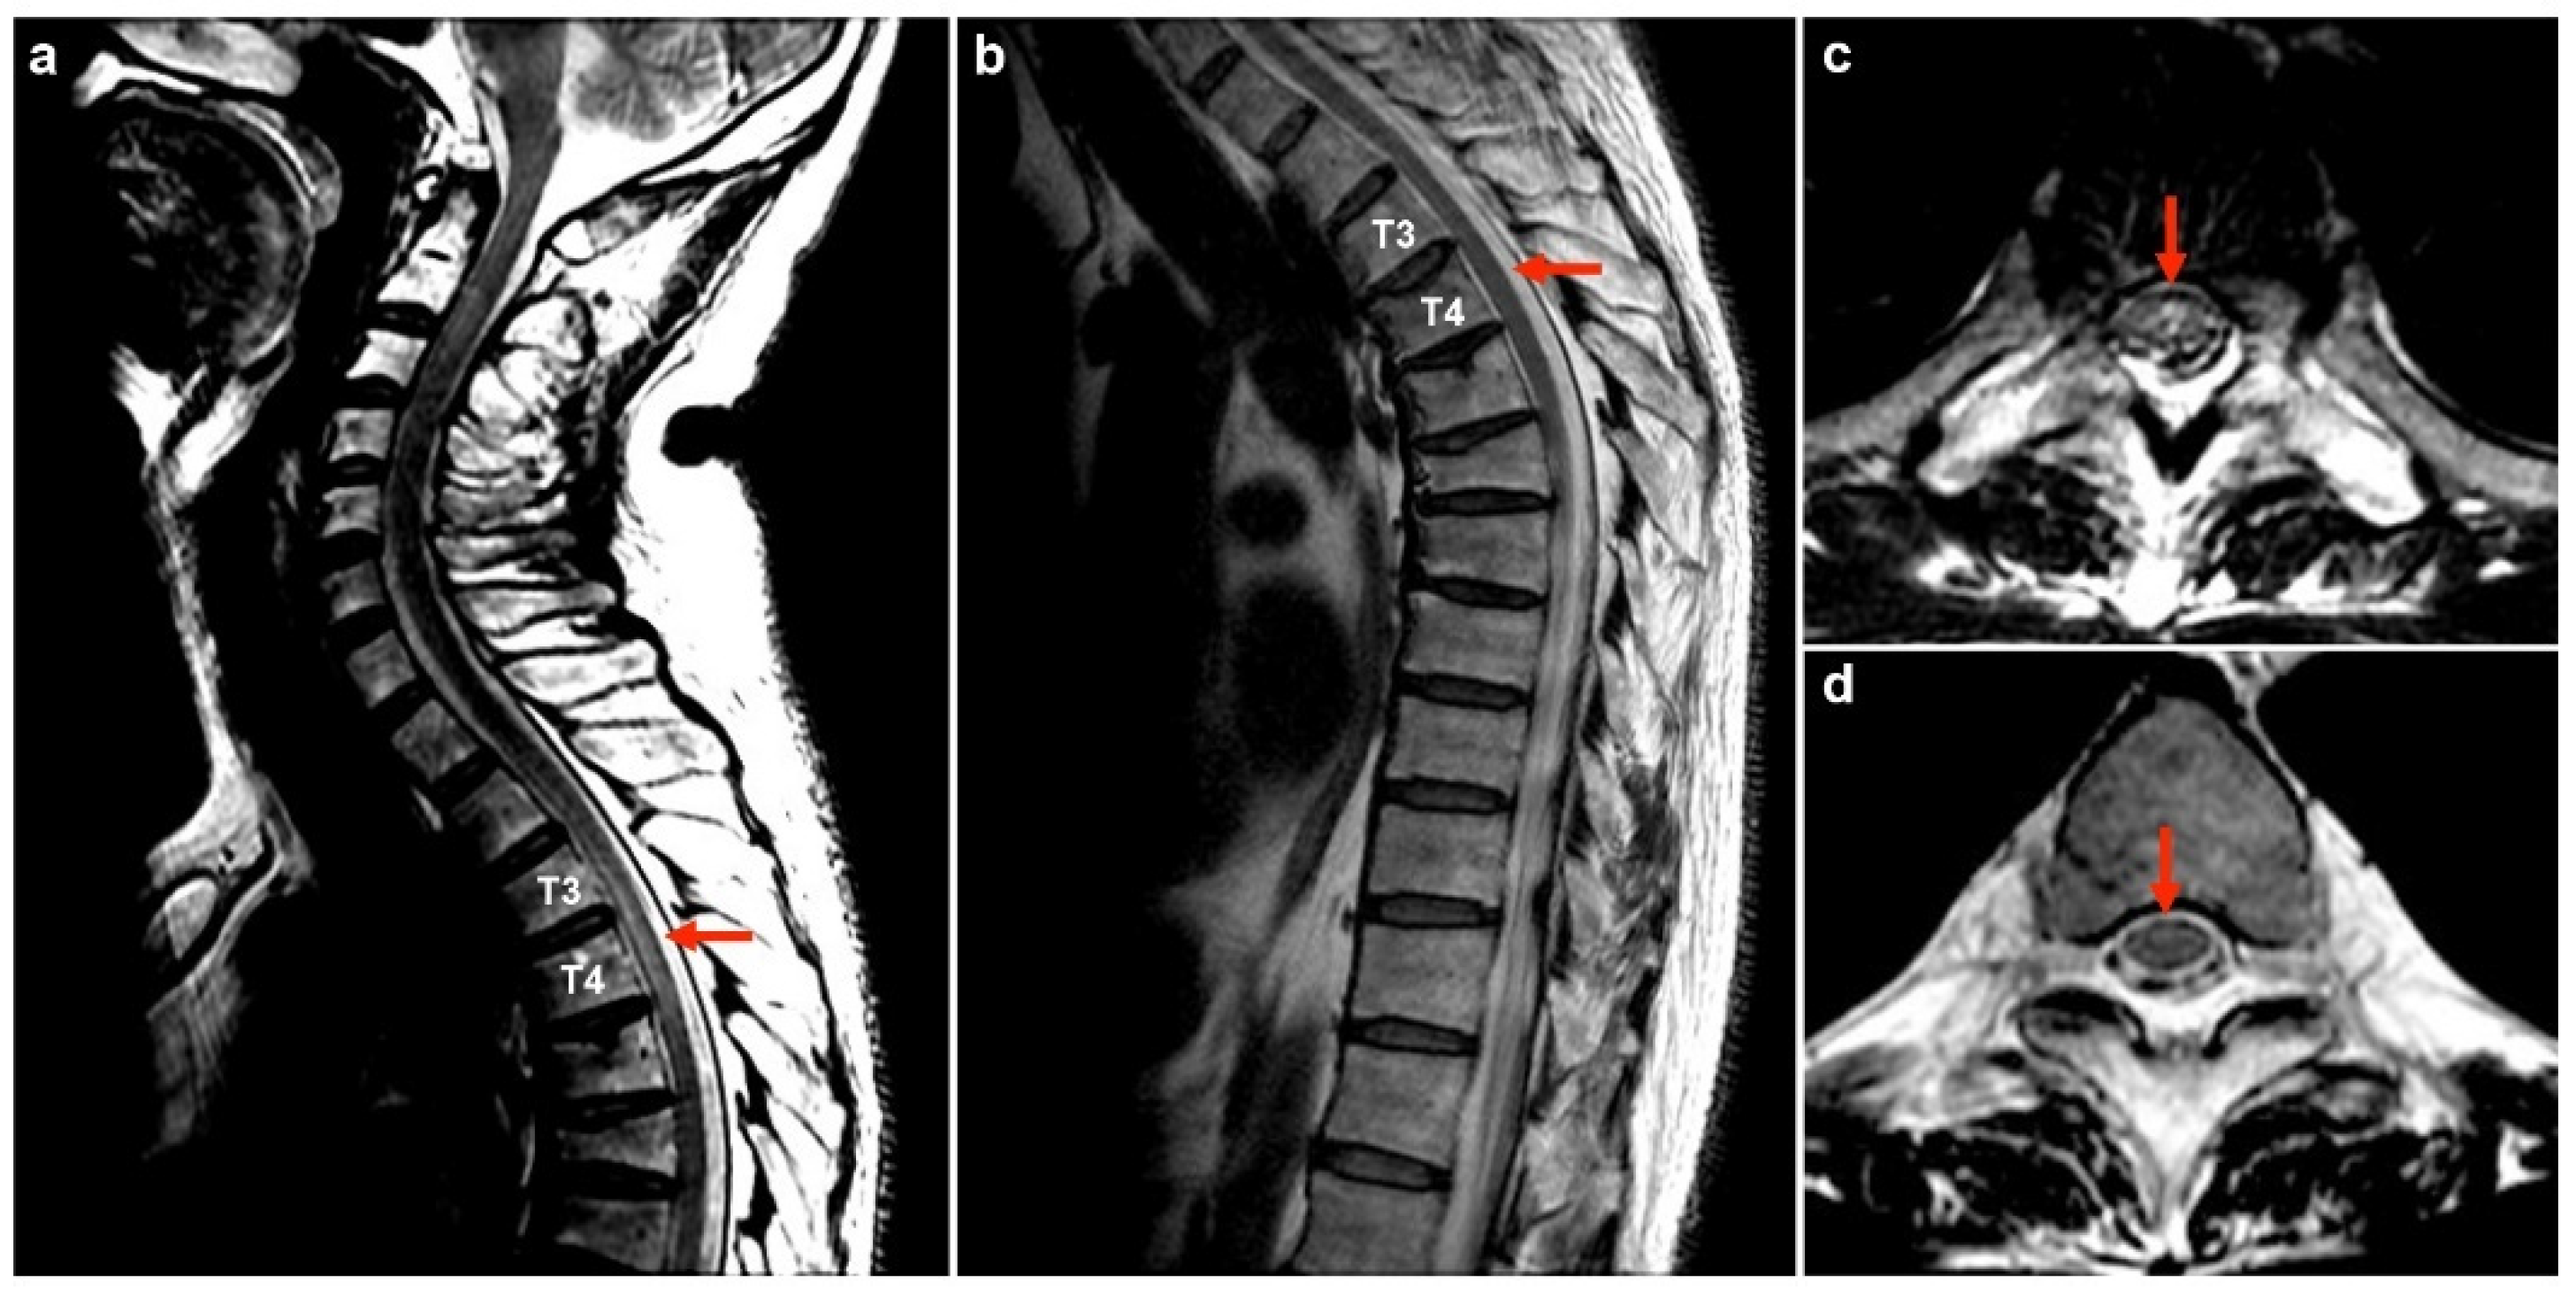

| 1 | 50M/HBV carrier | 1st AZ/13 | MOGAD | - | + | - | 175 | 99 | 0 | 78.1 | 0.47 | NA | Bil thalami, pu, subcortical WM, brainstem | T3-T4 | PT | R | Index case |